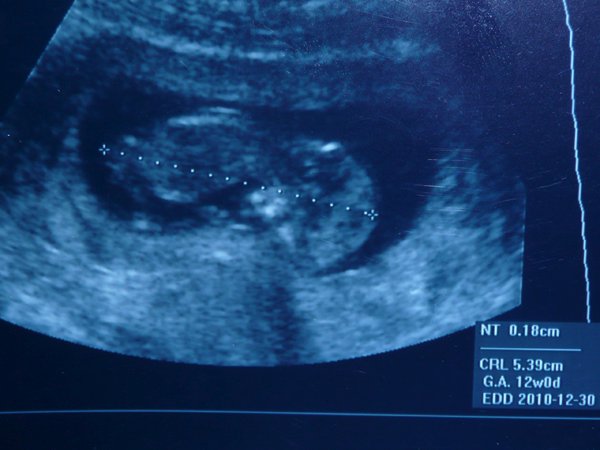

12 hetes UH: nálunk az az utolsó hüvelyi UH, tehát én még arra készülök, bár tegnap is megkérdeztem a dokim, hogyan vetkőzzek, felhúzzam, vagy lehúzzam